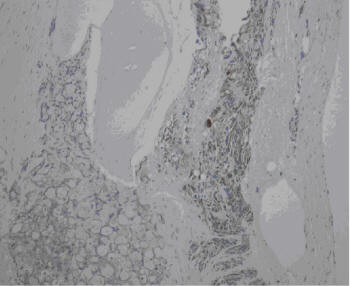

Fig2 - BioMed Central | The Open Access Publisher